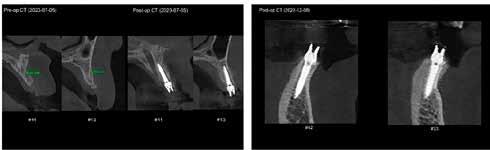

Dr. Markus Sperlich, dr. Mathias Sperlich (Németország)

AZONNALI IMPLANTÁCIÓ-

ÉS RESTAURÁCIÓKÉSZÍTÉS –A PONTOSSÁG ÚJ SZINTJE

A páciensek egyre inkább keresik a rövidebb és kevésbé invazív kezeléseket. Ezt friss kutatások és prospektív analízisek (1) is megerősítik, felhívva a figyelmet arra, hogy a hatékony, azonnali implantációra és restaurációra egyre nagyobb az igény. Rengeteg információ elérhető az interneten, ezért a páciensek manapság sokkal jobban informáltak a lehetséges kezelési opciókról. Az alábbi cikkben két fogorvos, Markus Sperlich és Mathias Sperlich átbeszélik az azonnali implantáció koncepcióját.

Az azonnali implantáció- és azonnali restaurációkészítés implantológiai koncepciója rendkívül előnyös, ugyanis a páciens pszichésen sem szenved akkora sérülést, és a szöveteket is sokkal jobban meg lehet tartani. Ez a módszer jelentősen lerövidíti a kezelést és a költségeket is csökkenti (2). A kezelés minimálinvazív, csökkenti a gyógyulási időt és gyors rehabilitációt tesz lehetővé, ezáltal jobb lesz a páciensek életminősége is. A kezelési eljárás jelentősen csökkenti a csontban a fogeltávolítást követően létrejövő dimenzionális változásokat (3–4).

Azonnali

implantáció –klinikai esetsorozat

Egy esetsorozatban 20 reménytelen prognózisú fogat távolítottunk el és azonnali implantációt végeztünk Straumann BLX implantátumok segítségével, amelyeket előre legyártott CAD/CAM koronákkal láttunk el közvetlenül az implantáció után. A műtétek előtt háromdimenziós, préoperatív tervezést végeztünk, minden esetben a SMOP Swissmedia tervezőrendszer segítségével (1. ábra), hogy meghatározzuk a protetikai szempontból ideális implantátumpozíciót az azonnali restaurációhoz. A sebészi sablont megterveztük és a szuprastruktúra dimenziót meghatároztuk a felépítmény geometriája alapján. A leendő implantátumpozíciók STL-adatát az SMOP háromdimenziós tervezőszoftverrel készítettük el és importáltuk a CAD-szoftverbe (exocad). Ezt követően a megfelelő restaurációkat legyártottuk (CAM) az exocad tervek alapján. Minden esetben csavarozható, akrilát szólókoronákat gyártottunk le a műtét előtt.

Klinikai munkamenet

Kezdésnek atraumatikusan eltávolítottuk az érintett fogakat (3. ábra), ezt követően előkészítettük az alveolust és azonnali implantációt végeztünk a megfelelő implantátummal (4. ábra). Amennyiben a behajtási nyomaték nagyobb volt, mint 35 Ncm, az implantátumra azonnal felcsavaroztuk az előre legyártott csavarozható koronát. Ehhez a beavatkozáshoz az előfeltételek: sértetlen posztextrakciós alveolus, egészséges lágyszövetek, gyulladásmentes környezet, valamint együttműködő páciens (5). A háromdimenziós tervezés nélkülözhetetlen az alább bemutatott munkamenet kivitelezéséhez (6–8). Csak a sablon által vezetett implan-

tátumbehelyezés teszi lehetővé, hogy a vertikális magasság és az implantátum belső kapcsolatának orientációja megegyezzen a digitális tervezéssel. Ezért a TorcFit kapcsolattal rendelkező Straumann BLX implantátumot pontosan úgy kell behelyezni, ahogy azt terveztük. A H07/H09/H11 behelyezőeszközök (5–6. ábra) speciálisan a mi praxisunkban lettek kifejlesztve, hogy meghatározzák a megfelelő vertikális implantátumpozíciót a sebészi sablon perselyeinek stop magassága által, valamint az angulációt és TorcFit belső kapcsolat megfelelő állását a pozicionálómarkerek segítségével (7. ábra). Az alábbi eljárás segítségével a későbbiekben kevesebb korrekcióra, becsiszolásra szorul az ideiglenes pótlás, ezáltal nincs szükség a műtéti terület mechanikai és kémiai manipulációjára, amely segíti a kezdeti zavartalan gyógyulást. A behelyezett korona felületét a laboratóriumban kialakított végső polírozott textúra adja (8.

ábra), a pácienst megkíméljük az egyéb, protetikai beavatkozásoktól (9). A következő paraméterek kulcsfontosságúak a siker érdekében (10): a páciensek megfelelő kiválasztása, a csont minősége és mennyisége, az implantátum dizájnja, 35 Ncm-nél nagyobb behajtási nyomaték (11), H07/09/H11 behelyezőeszközök és természetesen megfelelő sebészi tapasztalat. A digitális munkamenethez alapvető feltétel a digitális tervezés, amint azt bemutattuk (7).

Az előre legyártott pótlások sikeressége

Az alábbiakban bemutatott esetsorozatnál az előre legyártott pótlások illeszkedési pontossága elérte a 95%-ot, ahol bármilyen intraoperatív módosítás, alakítás vagy becsiszo-

2. ábra: Az előre legyártott pótlás tervezése az exocad szoftverben.

lás vált szükségessé, azt sikertelenségnek vettük. Az implantátumok sikerességi aránya 100%-os volt 18 hónap után (9–10. ábra). A előre legyártott azonnali pótlások protetikai sikerességi aránya 90%-os volt. Két esetben a korona levált a felépítményről az első hat hónap során. Egy összefoglaló elemzésben a szerzők összehasonlították a különböző implantátumbehelyezési és terhelési protokollokat (12). A cikkben az azonnali implantáció és azonnali terhelés 98,4%-os

sikerességi aránnyal szerepel. A hagyományos protokollok, ahol a késői implantációt hagyományos késői terhelés követi, a sikerességi arány 97,7%. Meg kell jegyeznünk azonban, hogy a szisztematikus áttekintésbe bevont cikkek között a bizonyítékok szintjében néha lényeges különbségek voltak, amikor az egyes protokollokat összehasonlították. Az azonnali implantáció adatai klinikailag dokumentált adatokra korlátozódtak.

Konklúzió

Az alábbiakban leírt munkamenet számos előnnyel jár, beleértve a maximális elégedettséget a páciens részéről, rövidebb kezelési időt és a meglévő szövetek optimális megőrzését.

A sikeres kimenetel a felsorolt követelmények szigorú betartásától és a megfelelő tapasztalattól függ. Számos magas evidenciaszintű tudományos tanulmány szükséges, hogy megerősítsük és konszolidáljuk ezeket az eredményeket.

9. ábra: Különböző stádiumnál készített röntgenfelvételek.

10. ábra: Kontroll 18 hónappal később.